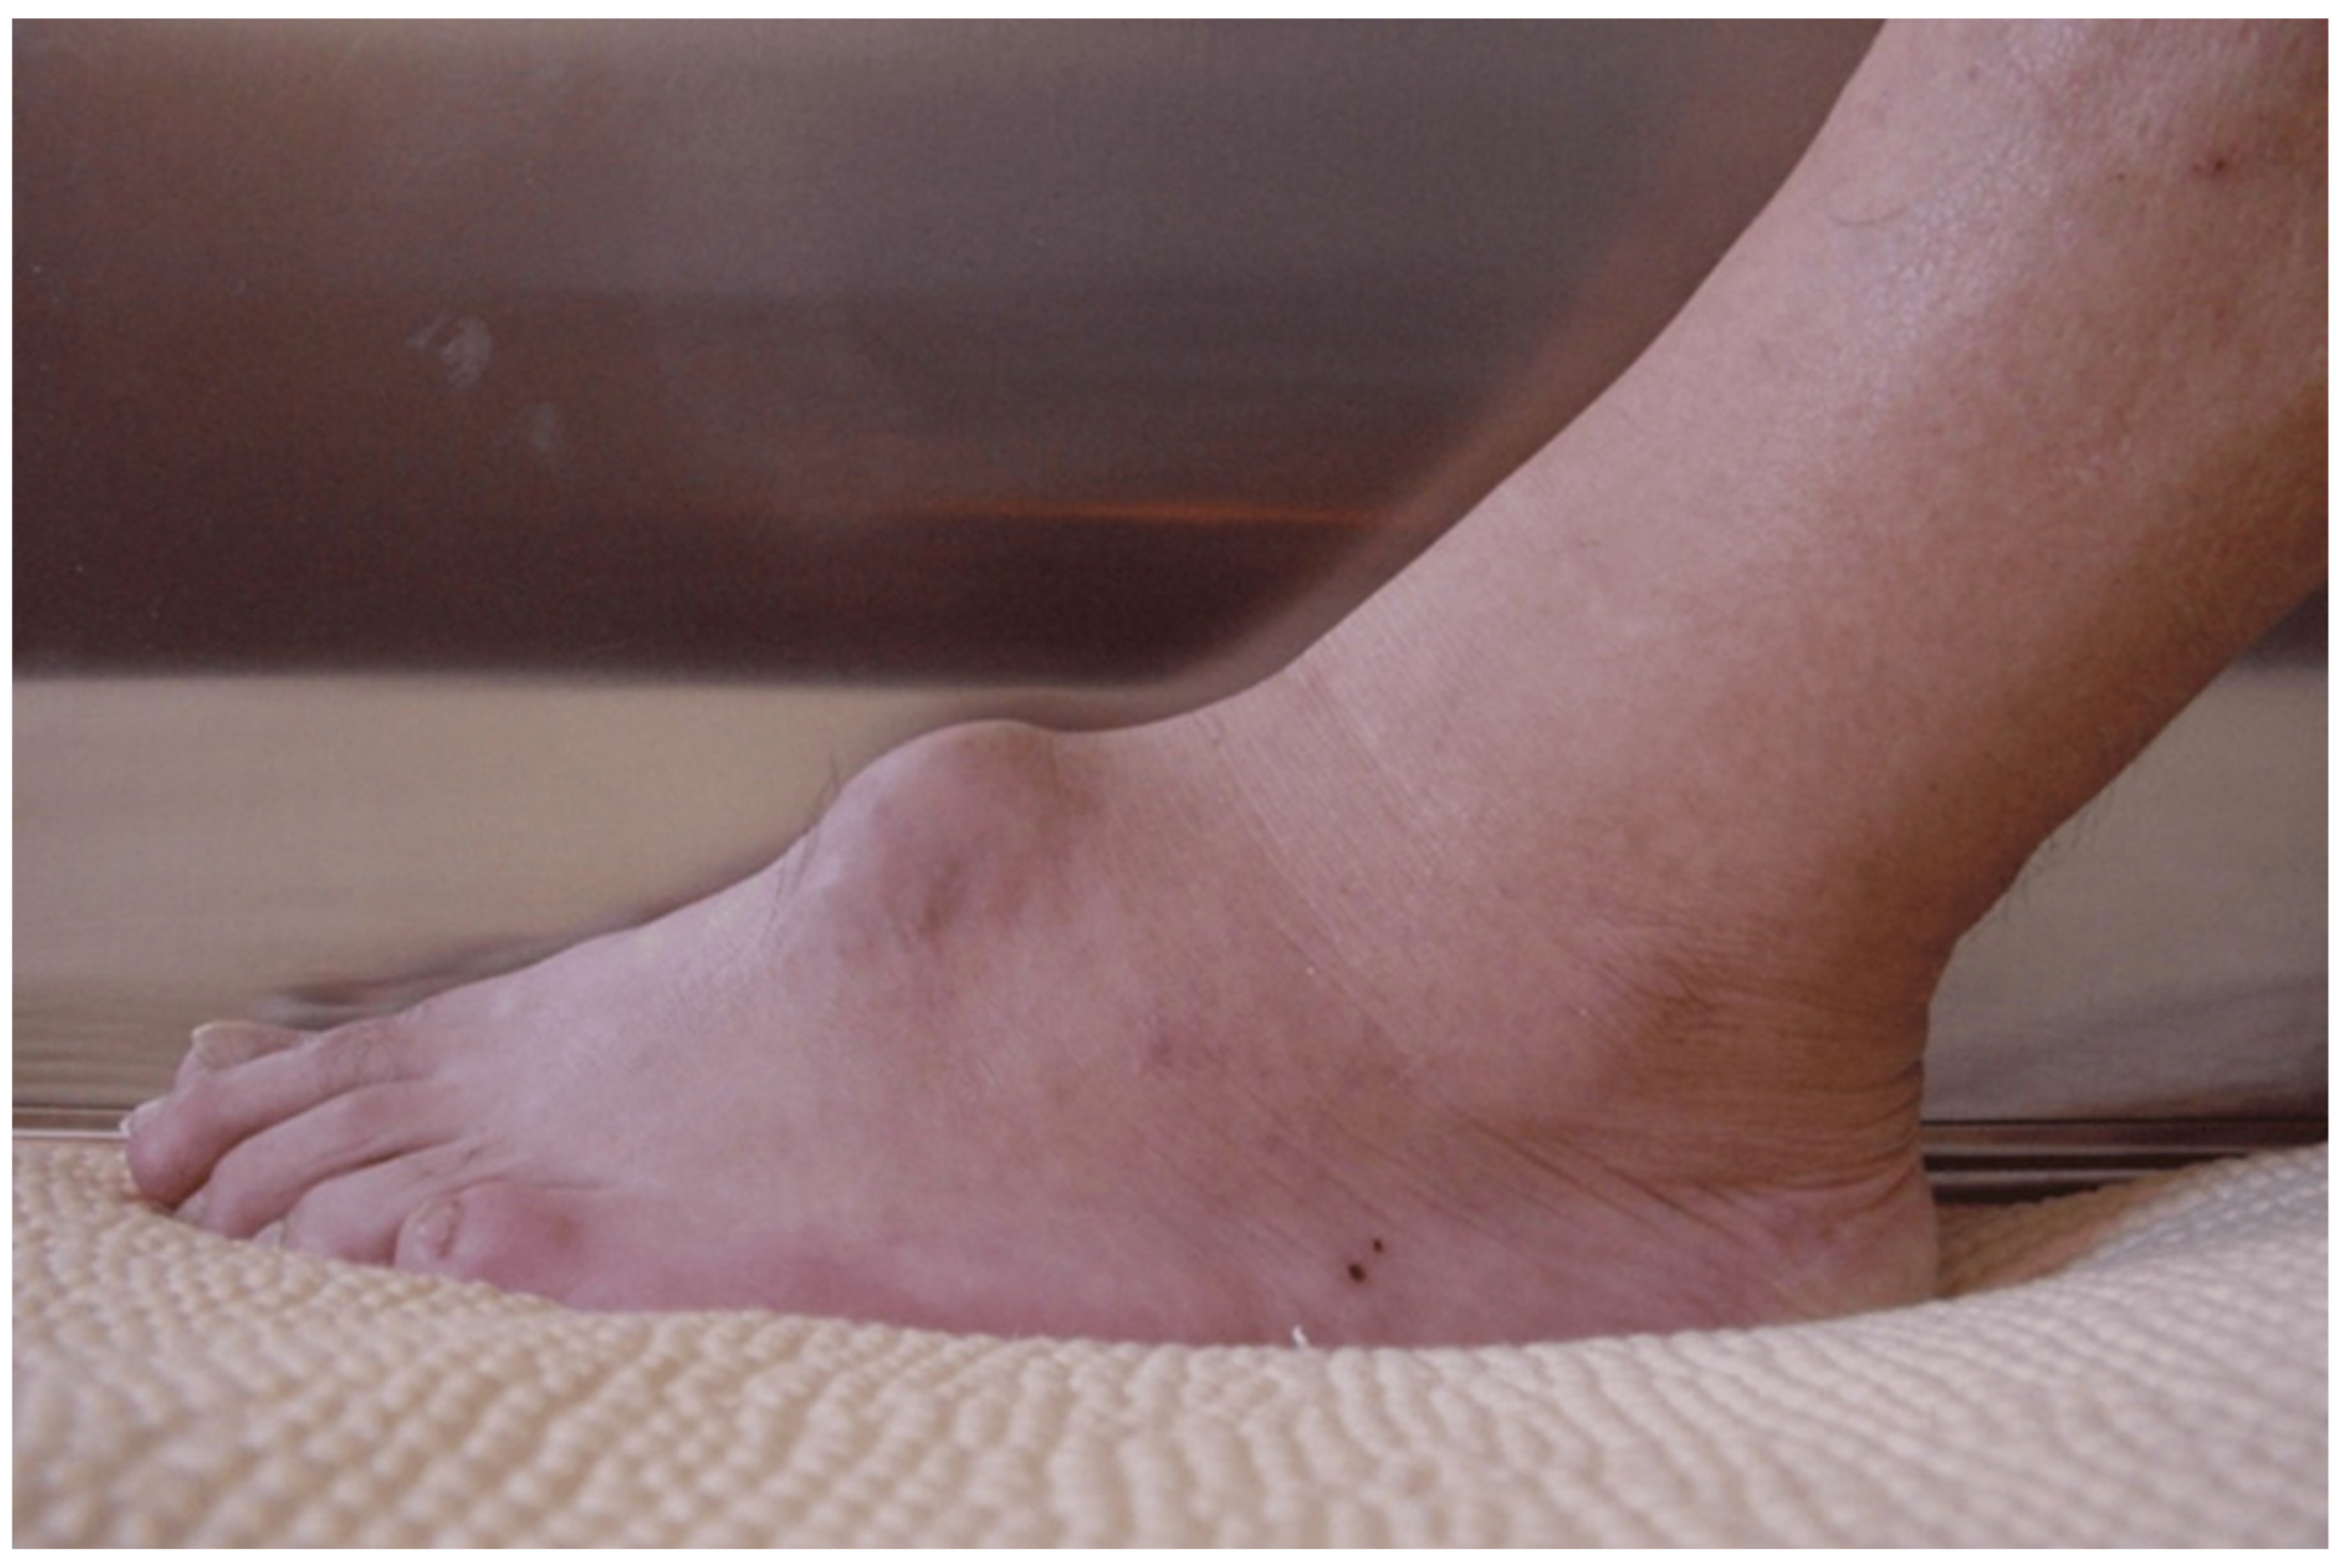

2. Epidemiology

3. Clinical Presentation